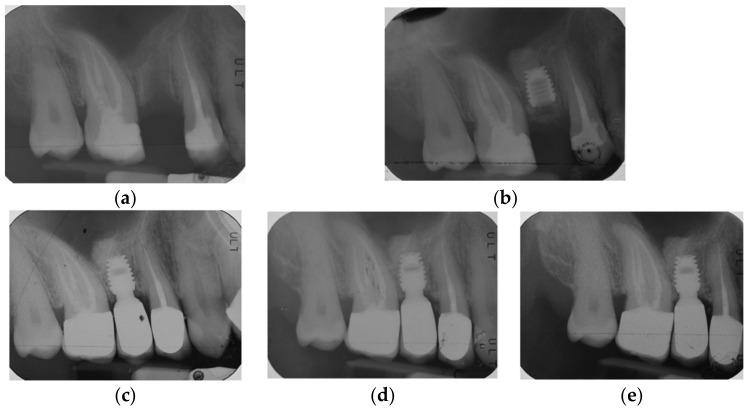

Recent short-term studies suggested the use of short and ultra-short implants in association with a modified osteotome sinus floor elevation (internal sinus lift) technique for the treatment of edentulous resorbed posterior maxilla. The aim of this retrospective study was to investigate this hypothesis in locking-taper implants with a mid-term follow-up of 5 years. Overall, 155 implants (32, 100, and 23 of, respectively, 5.0 mm, 6.0 mm, and 8.0 mm length) were positioned in the atrophic upper maxilla of 79 patients, and 151 implants were loaded with single crowns. Overall implant survival after 5 years was 94.84%. Implant survival for each length group was 93.75%, 94%, and 100% for 5.0, 6.0, and 8.0 mm length, respectively. Preoperative residual crestal bone height of 4.45 (1.3) mm increased to 9.25 (2.13) mm after implant placement and settled at 6.35 (1.73) mm after loading and at 5.25 (1.68) mm at follow-up. Elevation of the Schneiderian membrane was 4.8 (2.46) mm after implant placement, 3.06 (1.3) mm after loading, and 1.46 (1.06) mm at follow-up. Mean variations of peri-implant crestal bone loss and first bone-to-implant contact point were, respectively, -0.36 (1.3) mm and -0.62 (1.15) mm. It can be confirmed that internal sinus lift procedure revealed stable bone gain and negligible resorption at mid-term follow-up for atrophic upper crests with reduced height.

近期的短期研究表明,使用短种植体和超短种植体并结合改良骨凿上颌窦底提升术(内提升术)治疗上颌后牙区无牙颌吸收患者。本回顾性研究的目的是通过对锁定锥形种植体进行5年的中期随访来验证这一假设。总共155枚种植体(长度分别为5.0mm、6.0mm和8.0mm的种植体各32枚、100枚和23枚)植入79例患者的萎缩性上颌骨,151枚种植体上安装了单冠。5年后种植体总体存留率为94.84%。各长度组种植体的存留率分别为:5.0mm长度组93.75%,6.0mm长度组94%,8.0mm长度组100%。种植体植入前剩余牙槽嵴顶骨高度为4.45(1.3)mm,植入后增加到9.25(2.13)mm,加载后稳定在6.35(1.73)mm,随访时为(1.68)mm。种植体植入后上颌窦黏膜提升高度为4.8(2.46)mm,加载后为3.06(1.3)mm,随访时为1.46(1.06)mm。种植体周围嵴顶骨吸收和首次骨与种植体接触点的平均变化分别为-0.36(1.3)mm和-0.62(1.15)mm。可以确认,在内提升术中,对于高度降低的萎缩性上颌嵴,中期随访显示骨增量稳定且吸收可忽略不计。